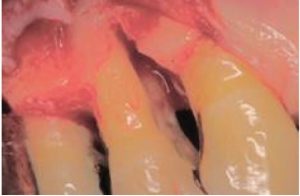

As previously mentioned, a dull or compromised scaler can lead to increased discomfort and decreased tactile sensitivity due to increased lateral pressure and number of strokes needed to remove the deposits. The cost of burnishing calculus, resulting in iatrogenic and supervised progression of periodontal disease when patients are placing their oral health in our hands cannot be measured (Fig 3,4). Breakage of a blade in a patient’s mouth, with possible need for surgical intervention due to using an over-worn working end is a preventable situation with a simple and quick check of the working end against a template.